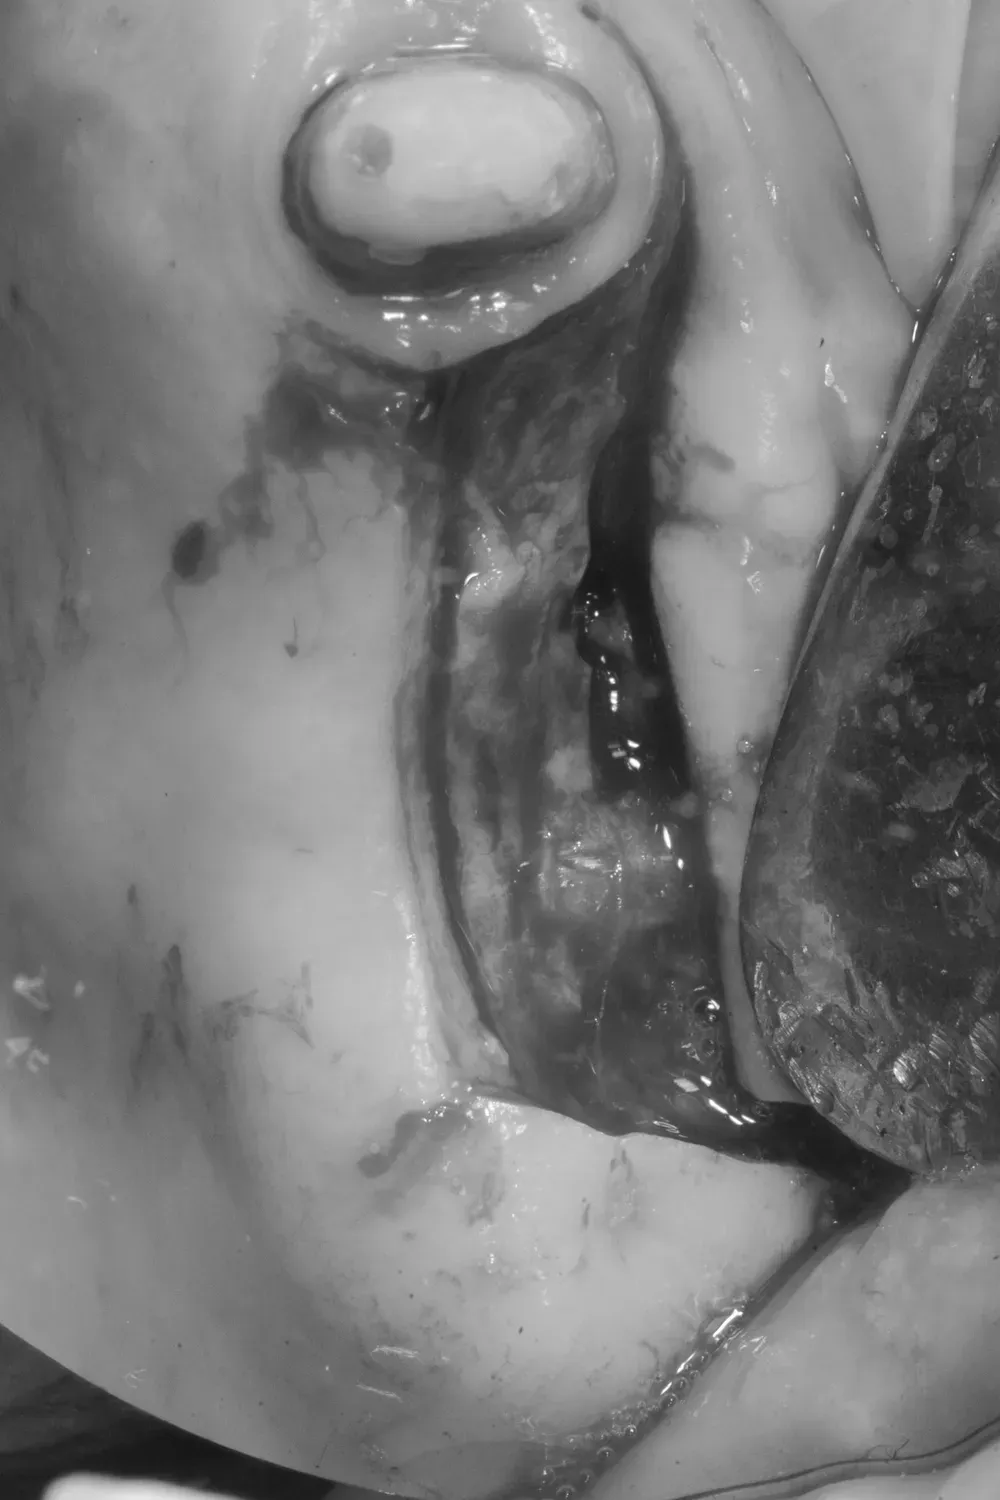

Di seguito potete vedere le foto intra-operatorie posteriori di destra e di sinistra:

Sul lato sinistro, l’atrofia dopo la rimozione dei denti e la rigenerazione era comunque meno grave e rientrava nell’ambito delle categorie S1-S2 CCARD. La prossima immagine è la CBCT della zona mascellare sinistra prima delle estrazioni.